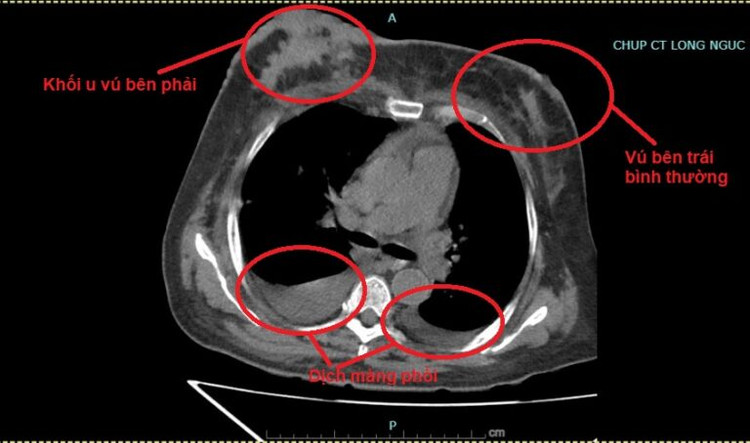

Ngày 7/12/2023, người bệnh nhập viện tại Trung tâm Ung bướu – Bệnh viện đa khoa tỉnh Phú Thọ trong tình trạng vàng da, khối u bên vú phải vỡ loét hoại tử, chảy dịch, 2 cánh tay phù nề. Sau khi thăm khám và thực hiện các chỉ định cận lâm sàng, người bệnh được chẩn đoán ung thư vú phải giai đoạn muộn (di căn gan, phổi)/Đái tháo đường, tăng huyết áp.

| Hình ảnh người bệnh có khối u vú bên phải và dịch màng phổi khi nhập viện |